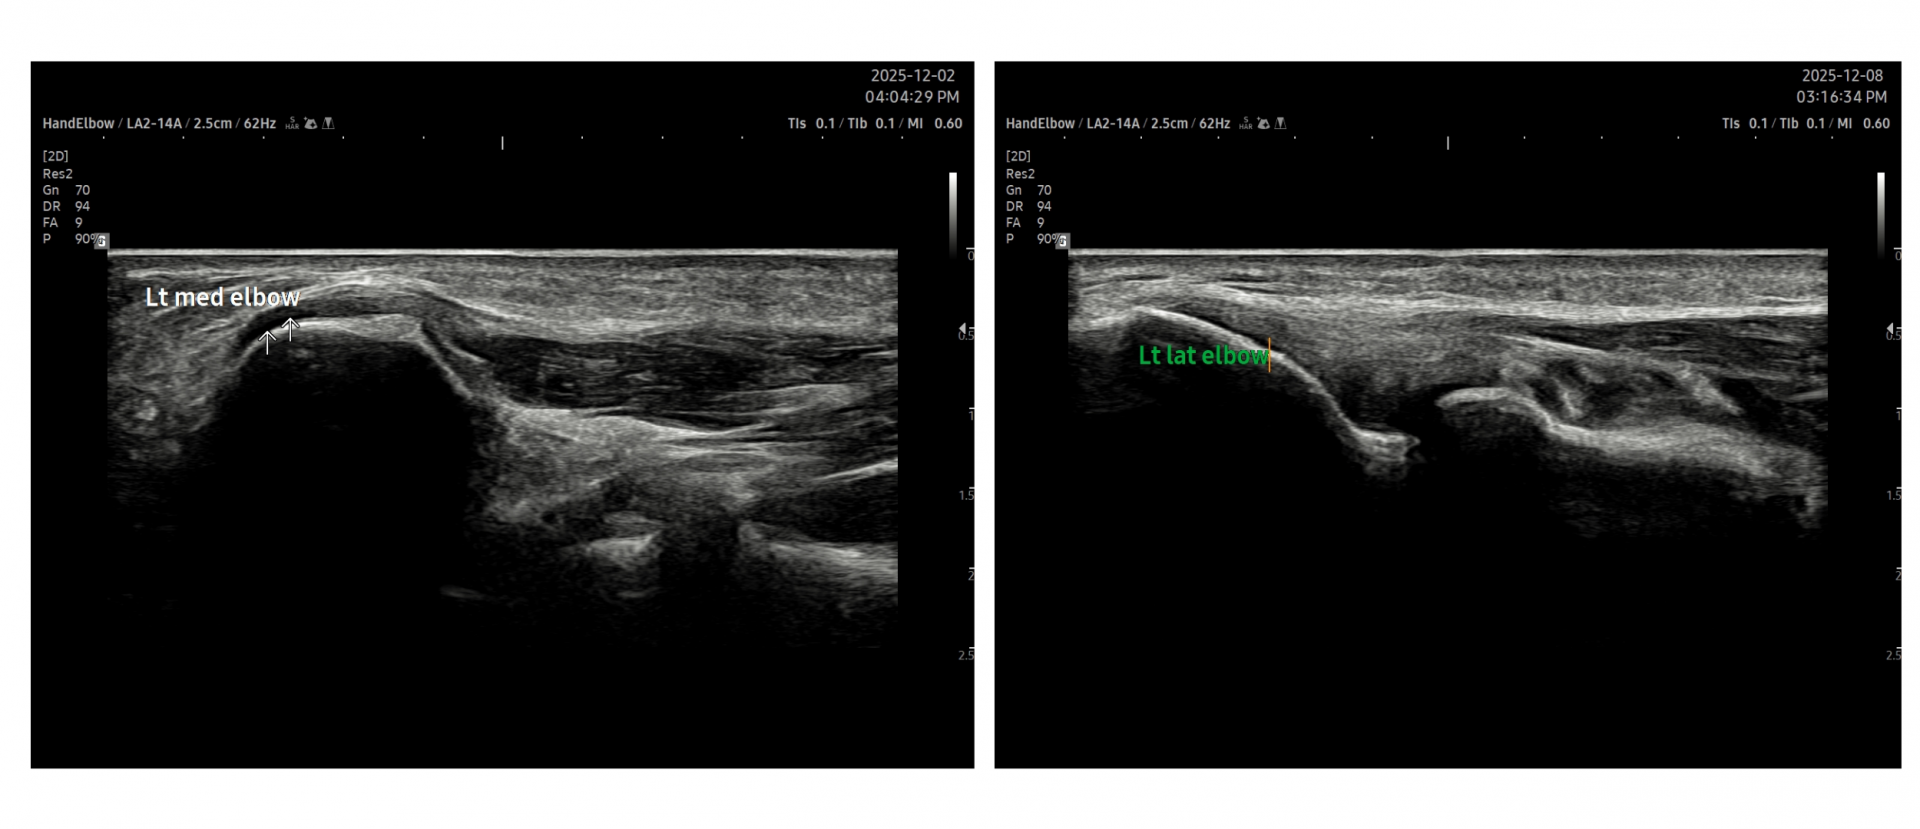

- 치료기간 : 25 . 8 .19 ~ 25 . 11 . 20

- 치료횟수 : 25 회 (사이클 치료 3 +아피톡신 10회)

치료 전

치료 후

좌측 골프엘보 : 12/2

좌측테니스엘보: 12/8

우측 골프엘보 : 12/2

우측 테니스엘보: 12/8